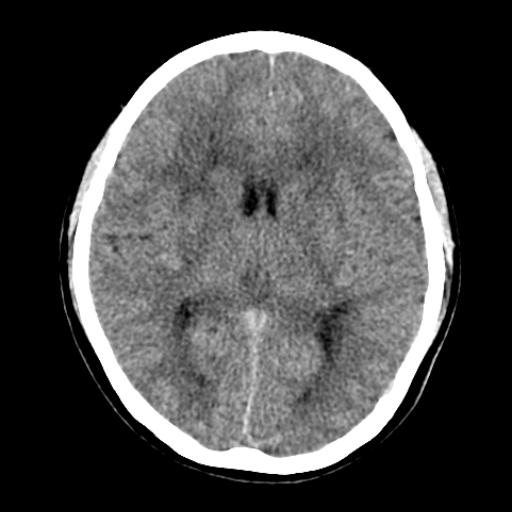

40f头晕十多天,右上肢麻木一天

脑白质变性或ms

脑白质脱髓鞘改变。

脑白质病;建议行mri检查。